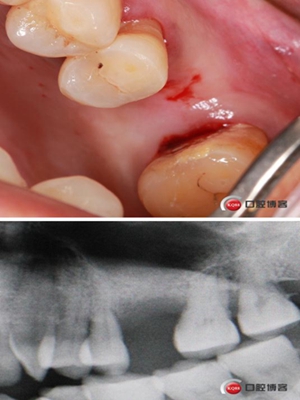

患者女性,58歲,身體健康,無(wú)不良咀嚼習(xí)慣,不吸煙、不飲酒。兩年前因左上后牙反復(fù)咬合痛,嚴(yán)重影響進(jìn)食就診,檢查發(fā)現(xiàn)26號(hào)牙根尖周炎癥明顯,周圍骨吸收嚴(yán)重。拔除患牙,徹底掻刮,由于骨缺損嚴(yán)重,沒(méi)能即刻種植。6個(gè)月后來(lái)門診種植。

骨高度僅有3mm,寬度充足。計(jì)劃外提升,根據(jù)骨質(zhì)情況決定是否同期植入植體,切開(kāi)翻瓣,暴露上頜竇頰側(cè)骨壁。